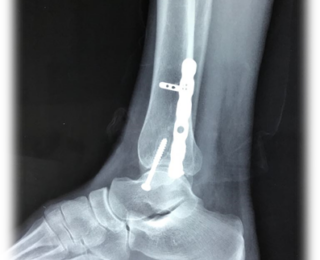

Masculino 20 años de edad, sufre fractura/luxación de tobillo derecho. Los accidentes en días festivos aumentan considerablemente fracturas en tobillo. Acude al servicio de urgencias donde se realiza diagnóstico y tratamiento: Fractura/luxación de tobillo derecho, ruptura de sindesmosis tibia peroné, ruptura deltoideo y capsula. Inmovilización, radiografías Ap y lateral de tobillo derecho, resonancia magnética nuclear, hospitalización, se usa técnica quirúrgica osteosíntesis y plastia deltoideo ligamentosa, abordaje lateral, placa y tornillos titanio especiales para tobillo. (TightRope de Arthrex) Cierre de sindesmosis tibio – peroné, sutura lado medial del ligamento deltoideo, cierre por planos y bota de fibra.

Anteroposterior y lateral (Figura 1). Entre los parámetros radiográficos que usamos para valorar la sindesmosis están; el espacio libre tibioperoneo, la superposición del espacio medial, ancho tibial y peroneal.

Osteosíntesis de peroné (derecho), cierre de sindesmosis y plástia de ligamento deltoideo con reconstrucción de maléolo izquierdo (TightRope de Arthrex).